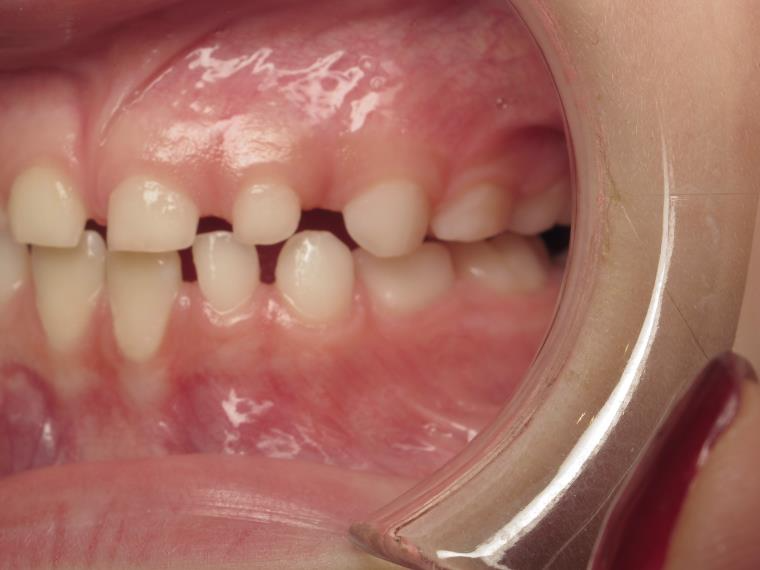

Sélectionnez les différentes étapes du traitement pour comparer et analyser la dentition du cas clinique.

bilan début et en cours de traitement